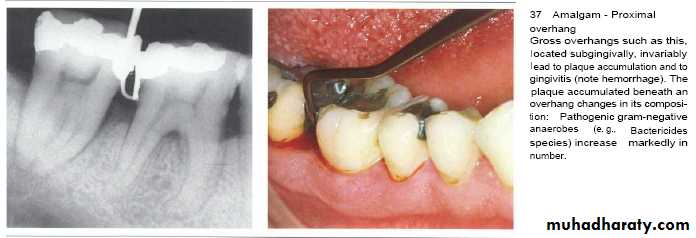

• Overhanging margins induce plaque accumulation & change

• the environment that allows growth of pathogenic bacteria &

• inhibit patient access to remove plaque.

• Subgingival placed restorations

Plaque accumulated are detected even with high quality subgingivally restoration, whereas supragingival restorations are similar to unrestored teeth.